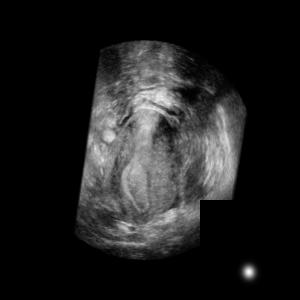

Standard plane (SP) localization is essential in routine clinical ultrasound (US) diagnosis. Compared to 2D US, 3D US can acquire multiple view planes in one scan and provide complete anatomy with the addition of coronal plane. However, manually navigating SPs in 3D US is laborious and biased due to the orientation variability and huge search space. In this study, we introduce a novel reinforcement learning (RL) framework for automatic SP localization in 3D US. Our contribution is three-fold. First, we formulate SP localization in 3D US as a tangent-point-based problem in RL to restructure the action space and significantly reduce the search space. Second, we design an auxiliary task learning strategy to enhance the model's ability to recognize subtle differences crossing Non-SPs and SPs in plane search. Finally, we propose a spatial-anatomical reward to effectively guide learning trajectories by exploiting spatial and anatomical information simultaneously. We explore the efficacy of our approach on localizing four SPs on uterus and fetal brain datasets. The experiments indicate that our approach achieves a high localization accuracy as well as robust performance.